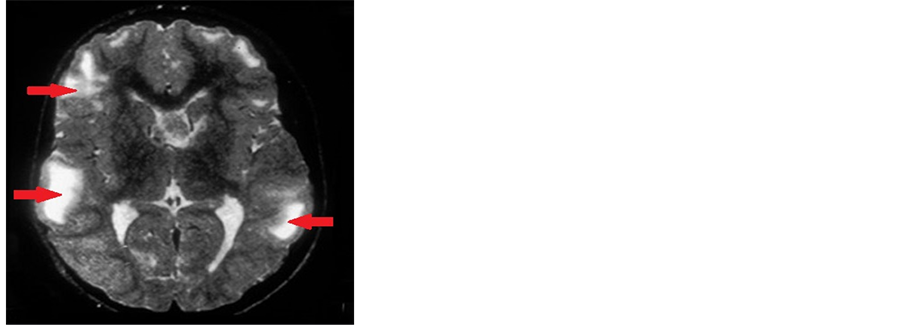

While his face showed facial angio-fibromatosis with butterfly distribution covering nose and spreading to cheeks. His skin examination revealed hypo-pigmented patches over the trunk and legs, with hypo-pigmented tuft of hair (Figure 3). Brain non contrast T2-weighted magnetic resonance image for the boy showed extensive high-signal cortical lesions typical of tuberous sclerosis (Figure 4).

Figure 4. Brain Non contrast T2-weighted magnetic resonance image for 6 y old boy, demonstrates extensive high-signal cortical lesions.

Brain changes for the girl was in the form of tubers throughout the cortex and mostly insubependymal regions giving rise to candle-dripping appearance, while for the boy MRI brain showed extensive high-signal cortical lesions typical of tuberous sclerosis. Sometimes the tuber converts to giant cell astrocytoma which may block the foramen of Monro resulting in hydrocephalus [20] . Due to cortical tubers the convulsion is a most common and early feature of this disease. Any type of convulsion from infantile spasm, myoclonic convulsion to persistent tonic convulsion may occur [21] . Both our patients had early onset convulsions, while the girl developed tonic- clonic convulsions at the age three months, the boy also developed convulsion at the age of four months and